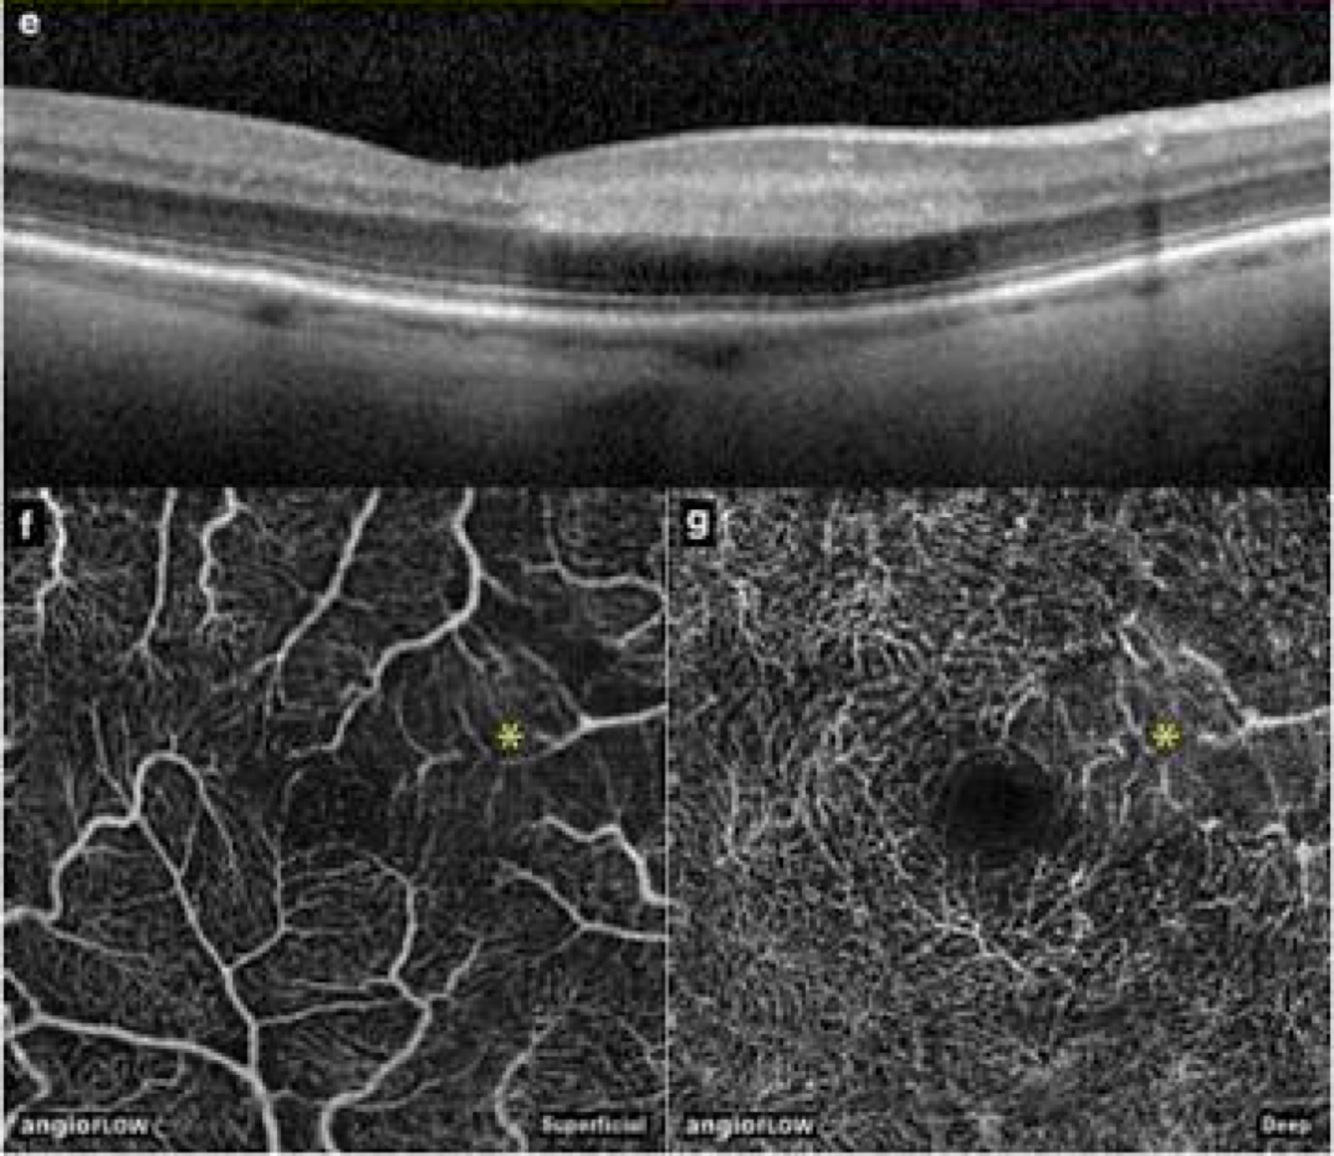

PAMM - maculopatia

50-60 anos, histórico de vasculopatia previa (oclusões, vasoespasmos)

Escotoma paracentral subito

OCT: hiperrefletividade camada intermediaria- nuclear interna (em banda ou salteado* melhor progn)

OCT - a : padrão samambaia

AGF: geralmente normal

• OCT-A: redução do fluxo no plexo intermediário